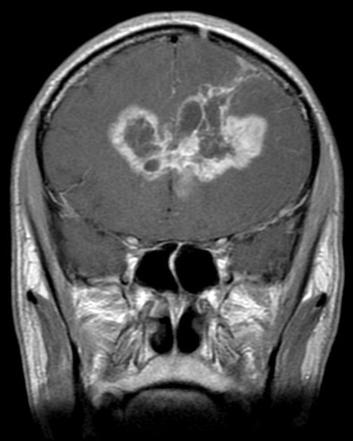

Glioblastoma (GBM) is one of the primary malignant brain tumors derived from glial cells of the central nervous system (Figure 1) Glial cells are responsible for supporting neuronal function, so one can imagine that uncontrolled growth of these cells can lead to serious neurological consequences affecting the functional processes of the brain GBMs originate from astrocytes and masses are found within cerebral hemispheres, as a “butterfly glioma” crossing the corpus callosum (Figure 2) In histopathological slides, GBMs present as poorly differentiated primitive cells with pseudopalisading necrosis (Figure 3)

Figure 3 Higher magnification showing nuclear pseudopalisading – aggregation of tumor cells around the periphery of the necrotic areas.

Johnston et al. found that pre-diagnostic MRI analysis of T1 images demonstrated hypointense lesions in LTS patients, with STS presenting with mixed-intensity lesions Gray matter involvement was mostly common in STS patients, but it is not a determinant characteristic and further imaging should be carried out T2/FLAIR hyperintensity was more common in LTS while there were no differences in T2/FLAIR heterogeneous signals between both groups One of the most significant results by show that contrast enhancement is significantly more prominent in wild-type IDH GBM patients Wang et al found that radiological features combined with IDH1 status for predicting the survival outcome of GBM patients showed that tumor contrast enhancement, multi-enhancing foci, and peritumoral edema, were found to be associated with the survival outcomes of GBM patients with IDH mutations.

Figure 3 – Adapted from https://www.webpathology.com/image.asp? case=738&n=13